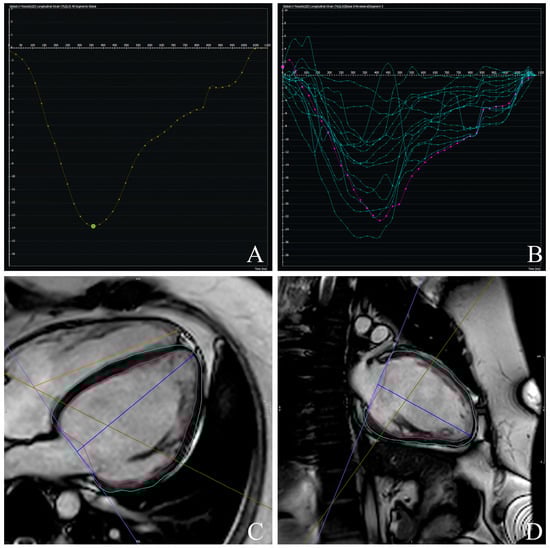

2.2. CMR Assessment

3.2. CMR-Derived Structural and Functional Parameters

3.3. Prognostic Value of CMR-Derived GLS

3.4. Prognostic Value of CMR-Derived LV-Torsion